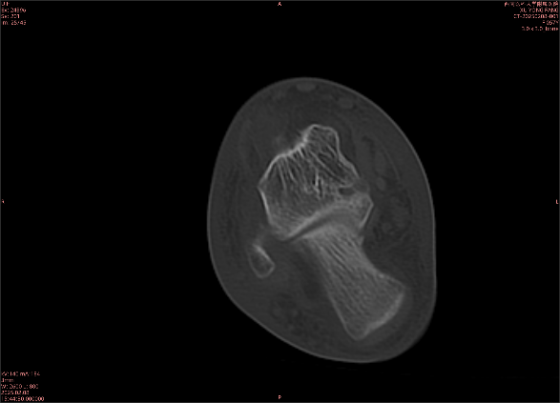

舉例圖像

圖2

專業(yè)解釋看不懂沒關(guān)系,大家看圖1和圖2就可以了,這是同一個患者跟骨的磁共振和CT圖像,圖1的紅色箭頭指示的黑線就是磁共振圖像顯示的骨折線,一目了然。而對比圖2的CT圖像上并未顯示異常。

這下大家明白了吧,如果懷疑隱匿性骨折優(yōu)先選擇磁共振檢查